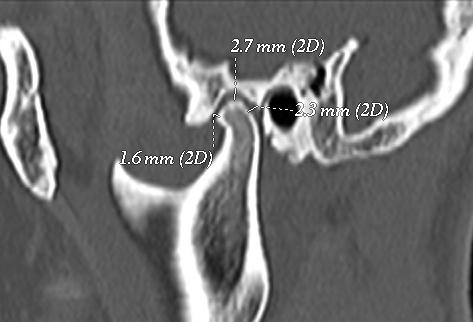

The temporomandibular joint (TMJ) is one of the most complex joints in the body and its harmonious functioning is very important to maintain a normal masticatory system. The morphologic alterations and the asymmetrical position of the TMJ structures may lead the various clinicalsigns & symptoms. Morphology of the temporomandibular joint may be influenced by gender of patients, environmental factor and also food habits at various places. Objective: To evaluate the morphology of the temporomandibular joint using computed tomography, in order to determine the condyle shape, joint space and glenoid fossa roof thickness. Material and Methods: One hundred and six healthy patients (212 TMJs) who visited a private hospital (or the University’s Hospital) for CT brain scan were included to this cross-sectional study sample.The patients were aged between 20–50 years with an average age of 35.46 years. All the images were taken by positioning patients in supine position with 120kvp , 50ma,2.33minute exposure with 0.7mm thick slicesby computed topography machine in all three projection that is Axial, Coronal and Saggital view. Results: For all variables, the mean and standard deviation were calculated, based on gender, and TMJ sides. The Paired t-test was used and P<0.05 will be considered to be significant. Conclusion: Present study showed that thereis positive evidence of temporomandibular joint involvement in elderly patients. Change in morphology and position of condylar head with glenoid fossa and roof thickness are one of the most common cause of degenerative diseases.